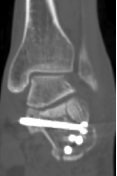

回到前文所述的患者程某,其X线片及CT检查提示其骨折系波及关节面的严重粉碎性骨折,具有明确的手术指征。

在骨科中心主任吴超的带领下,团队采用了天玑Ⅱ骨科手术机器人为程某开展了微创手术治疗,该手术时间短、创伤小、出血少、透视次数少,同时实现了骨折块的解剖复位和精准的螺钉置入及固定;术后影像学显示患者关节面完全复位,螺钉位置良好,固定可靠。